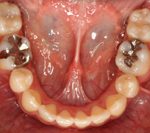

矯正の症例

1) 矯正前の状態

叢生(そうせい…歯がデコボコしたり、重なりあって生えていたりする状態)

開咬(かいこう…奥歯はしっかり噛んでいるが、上下の前歯が噛まずに隙間がある状態)